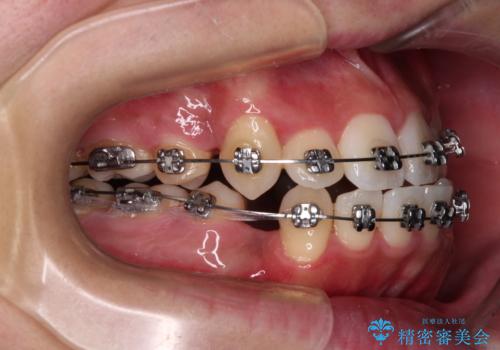

- メタルブラケット

- 2年4ヶ月

- 10-30回

上下ともに八重歯が顕著であり、前歯のクロスバイトがあったため、上下左右の第一小臼歯4本を抜歯し、ワイヤー装置での抜歯矯正を行うこととしました。